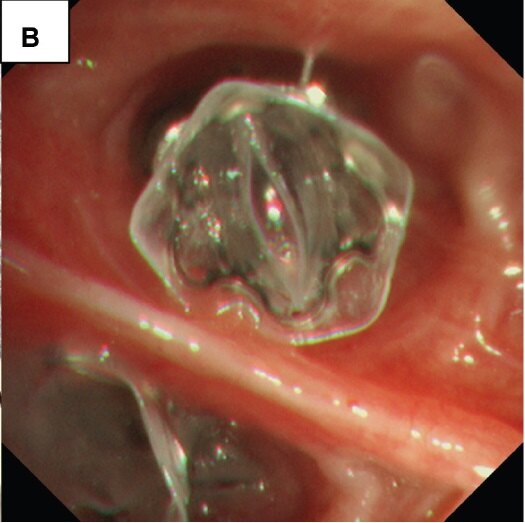

支气管活瓣减容是模拟肺外科减容的生理学效应,通过采用单向活瓣(放置于目标肺叶的亚段开口)将肺叶内过度膨胀的气体排出,造成局部吸收性肺不张。适用于无旁路通气的肺气肿。(当肺叶存在广泛的旁路通气时,本方法是无效的)

图A. EBV活瓣

图B. EBV活瓣放置于支气管亚段开口

具体操作之前,需要进行胸部CT扫描,以确认肺气肿,并确定肺气肿的分布情况及可能的目标肺叶。随后,在全麻下,进行支气管镜操作,植入活瓣。近年来,为了提高支气管活瓣治疗的有效性,需要排除有无旁路通气,在放置支气管活瓣前,借助于测漏系统,以判断有无寻找旁路通气。